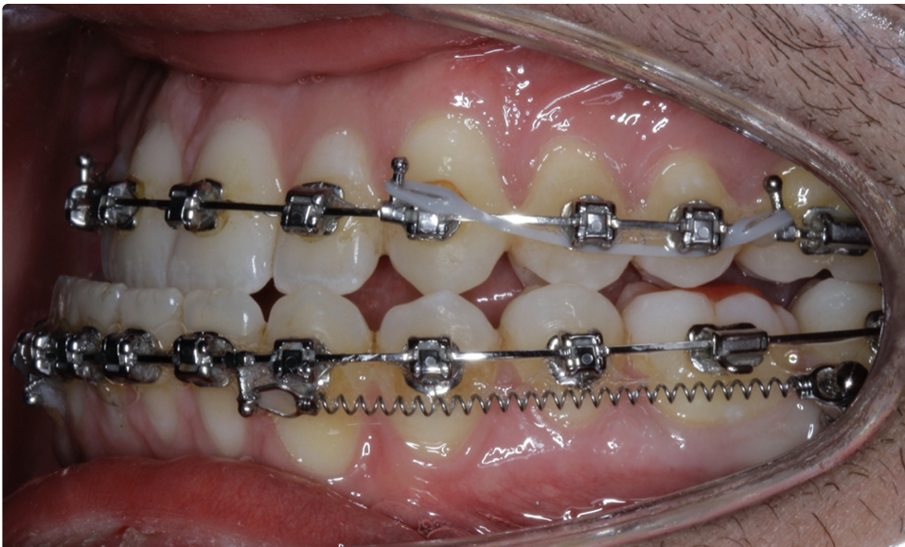

TADs are placed at the second visit with a 14 × 25 mm copper (Cu) and nickel–titanium (NiTi) wire and are tied from the anchor to the wire with an elastic thread (surgical thread; Fig. 6). Once the patient has progressed to larger Cu–NiTi wires and stainless steel, the TADs are tied to the wire using a power chain looped to the wire, or NiTi closing springs, depending on the thickness of the tissue (Figs. 7 & 8).